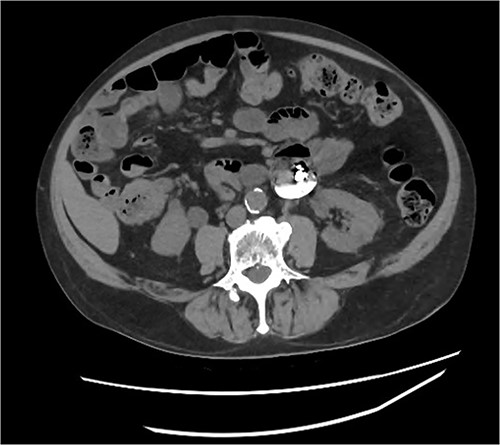

An 80 year old male presented to the emergency department after accidentally swallowing his hearing aids. On presentation he was pain free, hemodynamically stable, and had a soft abdomen. He had a background of type-2 diabetes, rheumatoid arthritis and diverticulitis. The hearing aids were powered by lithium battery. X-ray found two foreign bodies in the left upper abdomen (Fig. 1). After assessment in the emergency department, he returned home to await their natural passage. One hearing aid was found in his stools the following day, but he represented three weeks later as the second hearing aid remained unaccounted for. He underwent repeat abdominal x-ray and CT, which found the hearing aid retained within a presumed distal duodenal diverticulum (Figs 2 and 3). He was booked a push enteroscopy the following day.

Abdominal CT identifying one hearing aid in a jejunal diverticulum 3 weeks after initial presentation – axial view.